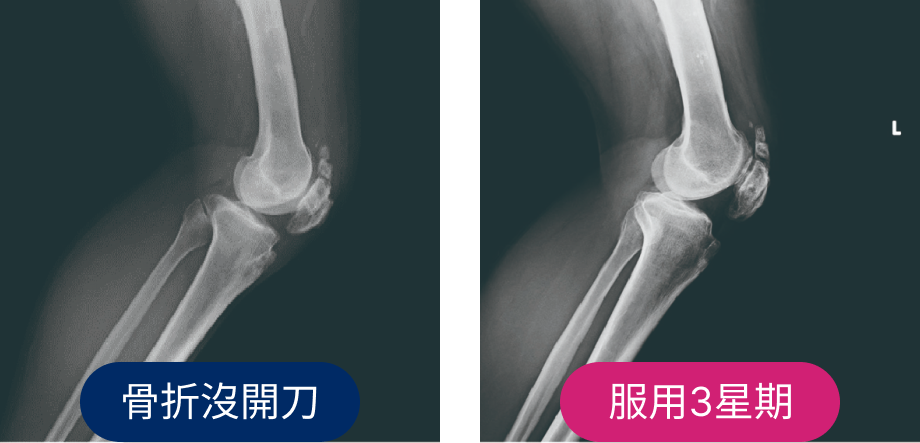

49歲男性

骨折仍渴望早日工作

廚師髕骨骨折,渴望早日工作,決定服用非晶鈣 服用3周後疼痛減輕,可以行走